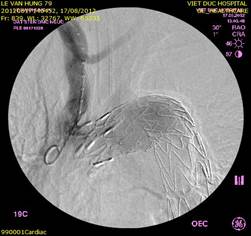

Ảnh: Hybrid trên quai ĐMC và tổn thương nhiều tầng của mạch máu:

Bắc cầu ĐM cảnh-cảnh P-T (BN 1) và đặt stentgraft quai ĐMC